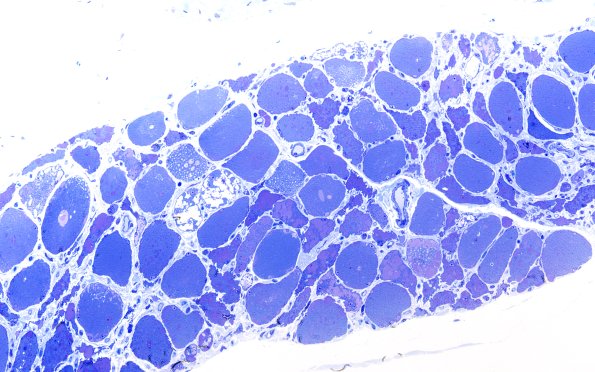

Washington University Experience | METABOLIC | Pompe Disease | 5C1 Muscle (Case 5) Plastic 100X 1

This is a one-micron thick toluidine blue stained plastic embedded section that shows marked variability in size of muscle fibers and a variety of individually altered fiber contents, seen at higher magnifications in the subsequent images. (Plastic section)